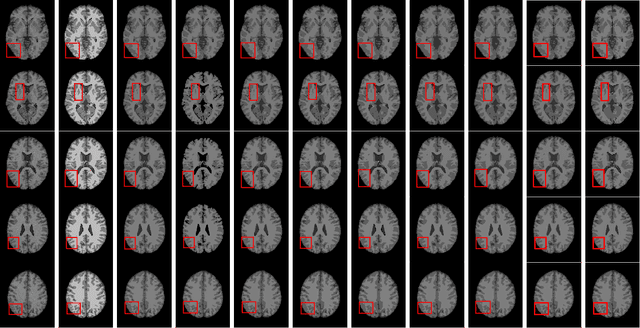

Abstract:Due to its inferior characteristics, an observed (noisy) image's direct use gives rise to poor segmentation results. Intuitively, using its noise-free image can favorably impact image segmentation. Hence, the accurate estimation of the residual between observed and noise-free images is an important task. To do so, we elaborate on residual-driven Fuzzy C-Means (FCM) for image segmentation, which is the first approach that realizes accurate residual estimation and leads noise-free image to participate in clustering. We propose a residual-driven FCM framework by integrating into FCM a residual-related fidelity term derived from the distribution of different types of noise. Built on this framework, we present a weighted $\ell_{2}$-norm fidelity term by weighting mixed noise distribution, thus resulting in a universal residual-driven FCM algorithm in presence of mixed or unknown noise. Besides, with the constraint of spatial information, the residual estimation becomes more reliable than that only considering an observed image itself. Supporting experiments on synthetic, medical, and real-world images are conducted. The results demonstrate the superior effectiveness and efficiency of the proposed algorithm over existing FCM-related algorithms.

Abstract:Although spatial information of images usually enhance the robustness of the Fuzzy C-Means (FCM) algorithm, it greatly increases the computational costs for image segmentation. To achieve a sound trade-off between the segmentation performance and the speed of clustering, we come up with a Kullback-Leibler (KL) divergence-based FCM algorithm by incorporating a tight wavelet frame transform and a morphological reconstruction operation. To enhance FCM's robustness, an observed image is first filtered by using the morphological reconstruction. A tight wavelet frame system is employed to decompose the observed and filtered images so as to form their feature sets. Considering these feature sets as data of clustering, an modified FCM algorithm is proposed, which introduces a KL divergence term in the partition matrix into its objective function. The KL divergence term aims to make membership degrees of each image pixel closer to those of its neighbors, which brings that the membership partition becomes more suitable and the parameter setting of FCM becomes simplified. On the basis of the obtained partition matrix and prototypes, the segmented feature set is reconstructed by minimizing the inverse process of the modified objective function. To modify abnormal features produced in the reconstruction process, each reconstructed feature is reassigned to the closest prototype. As a result, the segmentation accuracy of KL divergence-based FCM is further improved. What's more, the segmented image is reconstructed by using a tight wavelet frame reconstruction operation. Finally, supporting experiments coping with synthetic, medical and color images are reported. Experimental results exhibit that the proposed algorithm works well and comes with better segmentation performance than other comparative algorithms. Moreover, the proposed algorithm requires less time than most of the FCM-related algorithms.